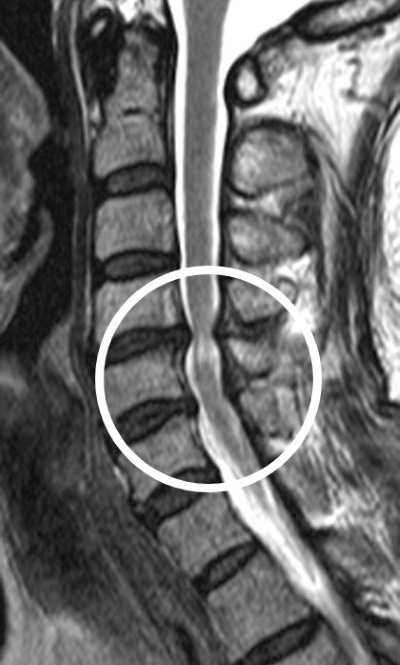

경추척수증은 경추(목뼈) 부위의 신경이 압박을 받아 손상되는 질환으로 손 움직임이 어렵거나 걷기 힘들어지는 등 운동신경·감각신경 마비를 유발할 수 있다.

▲ 경추척수증 환자의 경추 MRI = 경추 부위 척수신경(흰색 동그라미)이 압박을 받아 좁아진 모습이 나타남.

치료를 위해 척수신경이 지나는 부위(후궁)를 열고 압박을 풀어주는 ‘경추후궁성형술’을 실시한다. 이 수술 후 모든 환자는 예후를 추적 관찰하기 위해 수술 후 1년 동안은 수개월에 한 번씩, 2년부터는 매년 한 번씩 정기적으로 외래진료를 받아야 한다.